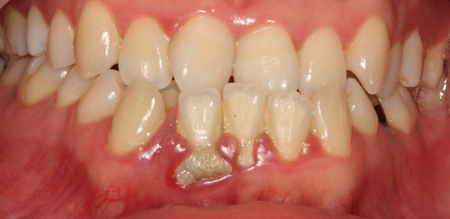

치주치료 전후사진

B

A

치주치료

청담네오플란트는 치주치료를 통하여 치아를 살릴 수 있는 기회를 놓치지 않습니다.

치주염(잇몸병)은 치아에 붙어있는 치석 및 세균 등에 의한 염증반응으로 잇몸뼈가 상실되는 질환을 말합니다.

초기에는 잇몸이 붓거나 잇몸에서 피가 나는 증상이 나타나며 계속 방치하면 치아를 발치해야 할 수도 있습니다.

치주치료는 이러한 치석 및 세균 등을 제거하여 잇몸뼈를 안정된 상태로 유지하는 시술을 말하며, 청담네오플란트에서는 치의학박사 / 전문의가 직접 시술하고 있습니다.